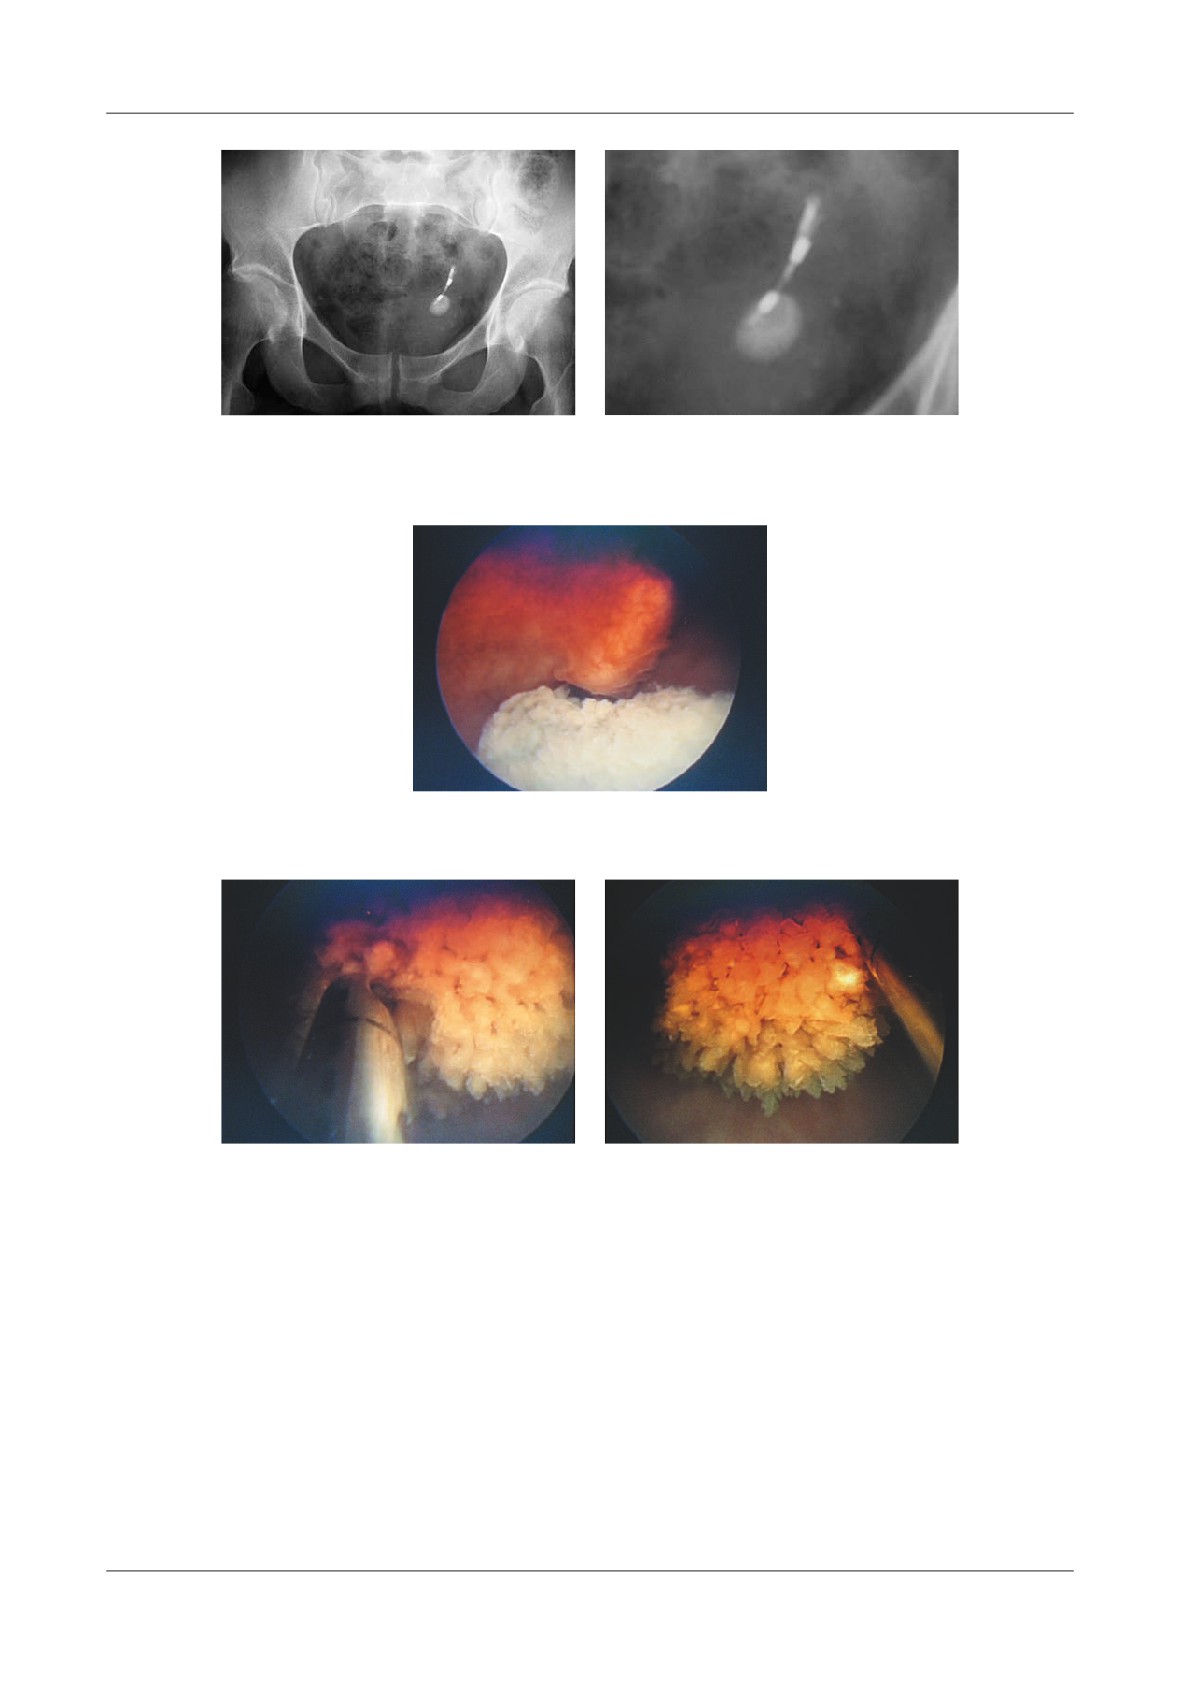

Figure 1. Pancreatic necrosis with the development of a pseudocyst, ileus and colonic in ltration in a 38

-year-old man. A-At admission the CT- shows enlarged pancreas and peripancreatic in ammation,  uid

(N=necrosis, P=pancreas, S=stomach), B-Lique ed necrosis nine days later with partially encapsulated

uid collection in the lesser sac, C-Dilated small bowel loops, with a haustral transverse colon. S=small

bowel, T=transverse colon, D-Five weeks later, fully encapsulated pseudocyst in the lower sac, with

lique ed necrosis in the neck of the pancreas (D=duodenum, N=necrosis, P=pseudocyst, S=stomach)

necrotic tissue (Figure 1).

Figure 4. Pancreatic pseudocyst secondary to necrosis.

A - Liquefaction necrosis in the tail, B - Large pseudocyst bulging into the stomach

Figure 5. Pseudocyst communicating with  the pancreatic duct, A-With CT image of enlarged gland

and peripancreatitis, B-After discharge from hospital, 2 weeks later, CT shows a residual collection,

C-6 months later, the patient had abdominal pain, CT shows an enlarging pseudocyst,

D-Trans gastric punction with  stulography, shows communication with the Wirsung duct